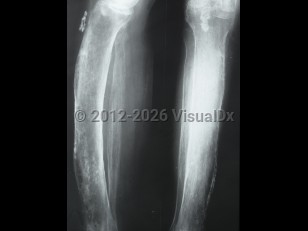

Periostitis

Inflammation of the periosteum, the covering of bones. Generally chronic, but may be acute.

- Chronic – Manifests with tenderness and swelling of the bone and an aching pain, and may be due to systemic inflammatory disorders.

- Noninfectious acute – Shin splints in athletes is a common cause.

- Infectious acute – Typically manifests with diffuse suppuration, severe pain, and systemic symptoms; it often results in necrosis.